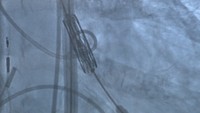

新たな心臓弁手術「TAVI」 高松赤十字病院が専門施設に認定

TAVI手術中の様子(高松赤十字病院 提供)

大動脈弁狭窄症に対する新しい手術法「TAVI」